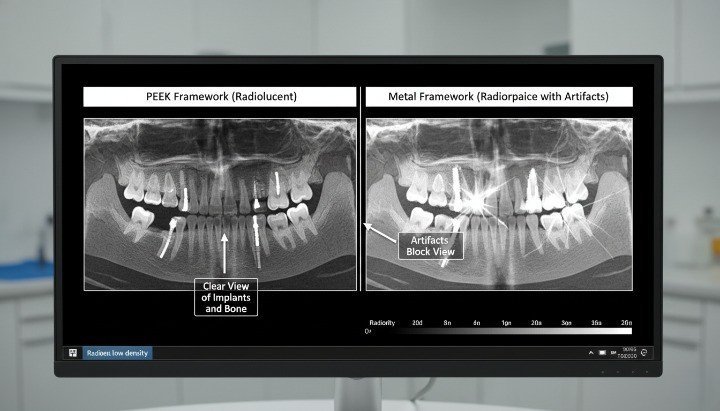

방사선투과성 및 영상화 이점

PEEK는 방사선 투과성이 있어 X선, CBCT 또는 CT 영상 촬영에 방해가 되지 않습니다. 따라서 의료진은 금속성 인공물 없이 주변 뼈와 연조직을 명확하게 시각화할 수 있습니다.

이러한 영상 투명성은 진단 및 추적 관찰을 향상시킵니다. 또한 변연골 수준 및 임플란트 주변 조직 건강 상태를 정확하게 평가하는 데 도움이 됩니다.

더 자세히 살펴보면, 방사선 투과성은 특히 임시 보철물, 치유 구성 요소 및 프레임워크에서 임상의가 치유 및 평가 단계 동안 방해받지 않는 영상 촬영을 원하는 경우에 매우 유용합니다.

방사선 촬영 및 MRI 호환성

PEEK는 방사선 투과성이 뛰어나 MRI 촬영 시 인공물 없이 사용 가능합니다.

티타늄은 영상 왜곡 및 빔 경화 현상을 유발합니다.